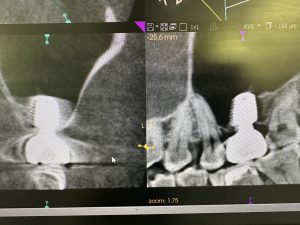

隔壁があり、難儀なデンサーリフトだったが、デンサーバーならではのリフティング💪

非常に良く安定している💪

今時、人工骨なんか使うは❌異物は洞内に入れない!

私もデンサーリフトで治して頂いた経験者‼️

間違いない!日本は遅れてるよね😭